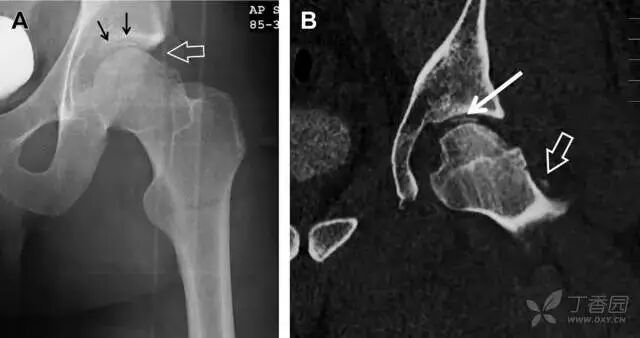

07非典型股骨骨折

另一种易漏诊的骨折是非典型股骨骨折,这种骨折与长期服用双膦酸盐相关,常发生在使用双膦酸盐 3 年以上的患者。前驱症状表现为腹股沟痛或大腿痛的患者中,60%~70% 被错误地认为由腰背痛或髋关节炎引起。

这种骨折的一个典型表现为火山口状骨膜隆起及一横行透亮带。值得注意的是,超过 50% 的患者表现为股骨干完全骨折。由于 50%~60% 的患者会累及双侧,所以一旦一侧下肢确诊,需行对侧下肢检查。

图 10 老年患者长期服用双磷酸盐引起的骨折。A 髋部正位片,箭头所示,股骨外侧皮质存在横行透亮带。B 后续的股骨 X 线片示局灶性骨膜反应,以及此类骨折的特征性表现-火山口状骨膜隆起(箭头)。C MRI 冠状位 STIR 序列扫描示相应骨折平面的骨髓水肿表现